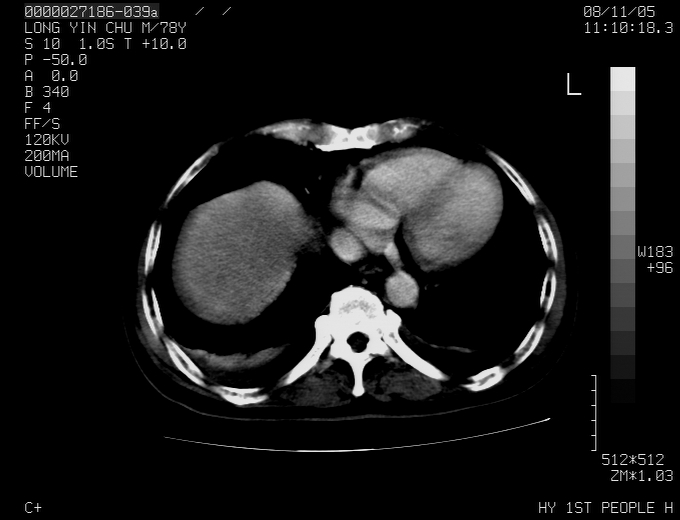

标题: CT16532:M78Y,肝脏病变,请会诊

腹胀,腹痛就诊,男性,78岁,外院b超未见异常。

肝ca,脾肾转移

考虑弥漫性肝癌并脾及双肾转移.双侧胸水.

肝脾肾转移瘤可能性大,左肾不除外梗塞,双侧胸水

考虑弥漫性肝癌并脾及双肾转移,双侧胸水。